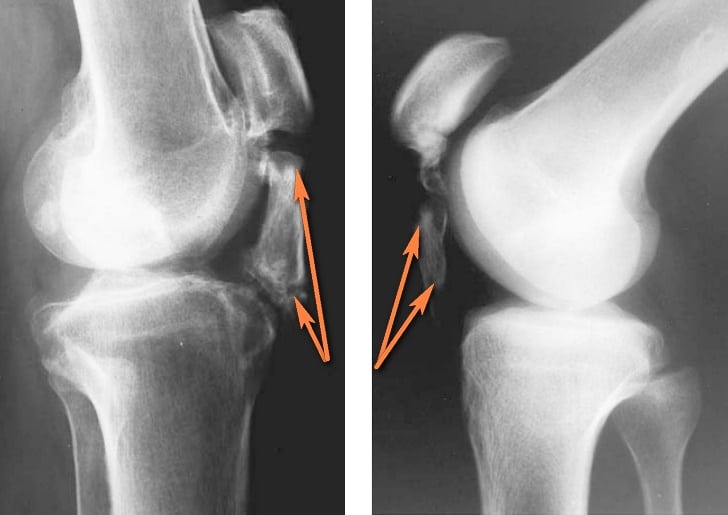

Иногда после рентгеновского снимка коленных суставов в заключении можно прочитать, что выставлен диагноз «лигаментоз». Какая разница между лигаментозом и лигаментитом? При лигаментозе имеет место уплотнение связочной ткани, повышение ее хрупкости вследствие избыточной минерализации или отложения солей. Этот процесс обызвествления связок наиболее часто протекает при нарушении обмена кальция в организме, например, при патологии паращитовидных желез. Лигаментит колена при рентгеновском исследовании будет «прозрачной» патологией, а при лигаментозе возникнут рентгеноконтрастные тени связок. Какими способами еще можно поставить диагноз?

Недуг на рентгене.

Окостенение связок обычно происходит в месте их крепления к костям.

Рентгенологическое исследование. На снимках видны участки затемнения в связках – очаги замещения хрящевой ткани на костную. Такие изменения характерны для поздних стадий болезни. Начальные изменения при лигаментозе рентгенологическое исследование не выявляет.

Только при помощи дополнительных методов обследования, самые важные из которых – рентген и УЗИ. Сочетание этих двух методов дает точную картину – какие ткани и в каком месте подверглись окостенению. Хорошо видны также избыточные костные наросты, если они успели образоваться.